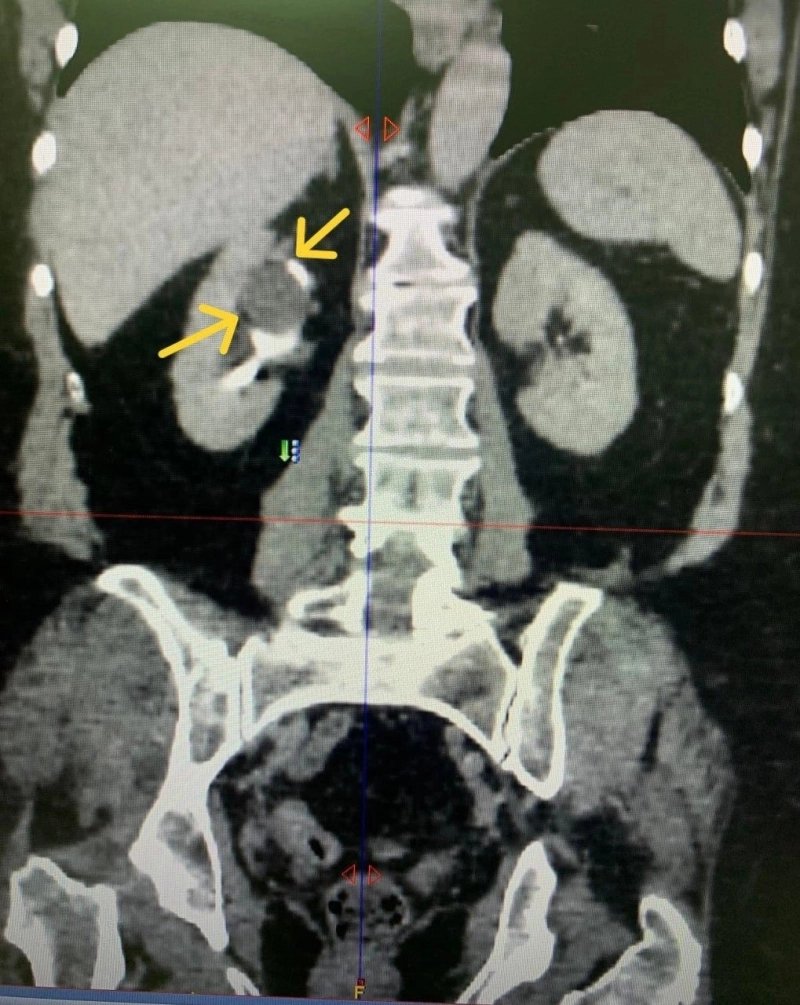

В Ульяновске 11 ноября врачи областного клинического центра специализированных медицинских услуг успешно завершили редкую хирургическую операцию. Урологи удалили одновременно камень и кисту из почки пациентки, страдающей мочекаменной болезнью.

Во время медицинского обследования женщины, которая обратилась в клинику с проблемами, связанными с камнями в почках, выявили парапельвикальную синусовую кисту. Она затрудняла естественный выход камня из верхней чашечки почки, что требовало срочного вмешательства. В ходе операции врачи использовали метод контактного лазерного дробления для удаления камня из мочеточника, одновременно устранив стенку кисты и освободив ее содержимое.